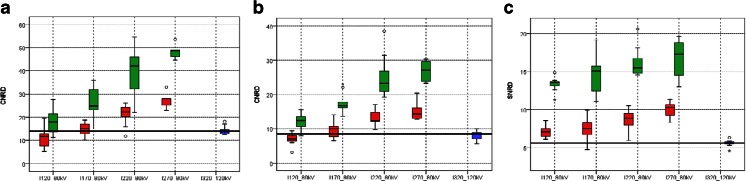

Compared to the (120 kVp, 320 mg I/mL) reference protocol, the (80 kVp, 270 mg I/mL) study protocol resulted in higher CT values in the abdominal aorta (Fig. 2, Table 3). There was no significant difference with the next lower concentrations 220 and 170 mg I/mL, whereas a concentration of 120 mg I/mL yielded inferior enhancement. In liver parenchyma during the portal venous phase, both study protocols with 270 and 220 mg I/mL resulted in higher CT values, and 120 mg I/mL yielded inferior enhancement. This was also observed for the portal vein. The median CTDIvol of the reference protocol scans was 7.8 mGy (CI 6.8–8.4 mGy). Hence, we dose normalized all noise values to a reference of 8.0 mGy and employed this to calculate CNRD and SNRD data (Fig. 3, Table 3). From the noise versus dose regression analysis, the following exponents were observed for FBP (a = −0.498 with r 2 = 0.96), ASiR (a = −0.508 with r 2 = 0.95) and Veo (a = −0.232 with r 2 = 0.94). Consequently, dose normalization was performed for FBP and ASiR with a = −0.50, as in the experimentally confirmed model, and for Veo with a = −0.23.

Fig. 2.

Box and whisker plots of CT enhancement in abdominal aorta (a), portal vein (b) and liver parenchyma (c). Each protocol is labeled by its combination of iodine concentration (I from 120 to 320 mg I/mL) and tube voltage (80 or 120 kVp). The solid line in the box represents the median value and the upper and lower bars represent the first and third quartiles respectively, whiskers represent the 95 % confidence interval. The bold reference line in the graph represents the median value of the reference protocol

Fig. 3.

Box and whisker plots of radiation dose normalized quantitative image quality (CNRD and SNRD) in abdominal aorta (a), portal vein (b) and liver parenchyma (c) with ASiR (red boxes) and Veo (green boxes) reconstruction. Each protocol is indicated by its combination of iodine concentration (I from 120 to 320 mg I/mL) and tube voltage (80 or 120 kVp). The solid line in the box represents the median value and the upper and lower bars represent the first and third quartiles respectively, whiskers represent the 95 % confidence interval. The bold reference line in the graph represents the median value of the reference protocol

In the abdominal aorta, all study protocols with ASiR reconstruction, apart from 120 mg I/mL, resulted in higher or non-inferior CNRD values. Owing to their increased noise suppression, all Veo protocols resulted in markedly higher image quality. The same trend was observed for the portal vein. In the liver parenchyma, all study protocols resulted in higher SNRD values for both ASiR and Veo reconstruction. With all ASiR study protocols, soft tissue noise in the dorsal muscle was comparable (SD range 14.8–20.8) to that in the reference protocol (SD 17.9). Veo reconstruction significantly reduced soft tissue noise values (SD range 9.0–11.3).